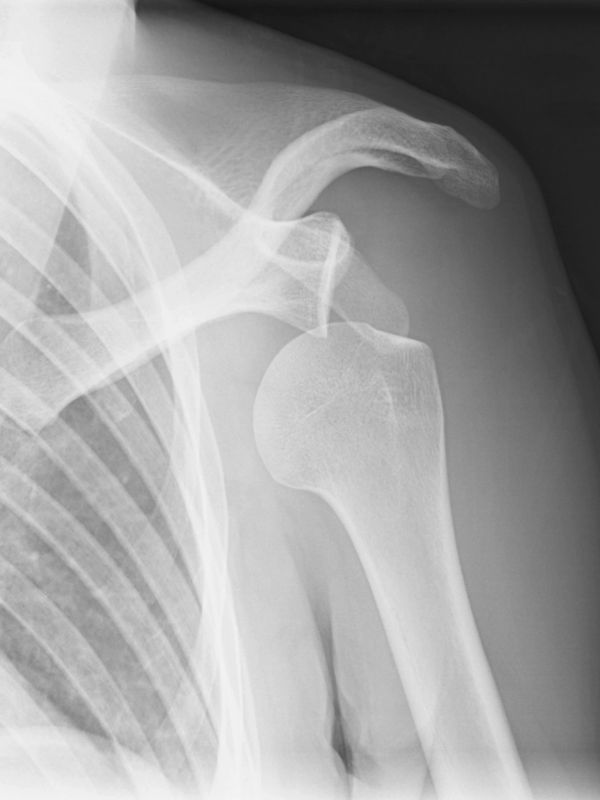

We'll cover glenohumeral subluxations & dislocations, acromioclavicular injuries and instabilities, sternoclavicular instability and the all important (and globally confused) scapular dyskinesis (in all its variations).

Day 1 will bring you up to speed on management of GHJ subluxations & dislocations, initial dislocation management and how it differs for recurrent dislocations. Non-operative vs operative considerations, picking the right surgical procedure (and surgeon), exercise management and necessary progressions.

A patient sees you for advice and rehabilitation options for a recurrent GHJ dislocation (*3), occurring on moderate overhead force. Current rehabilitation has consisted of rotator cuff exercise for the past month in various positions and range of motion drills. She does not feel confident with overhead movement, despite full range of motion and improvements in her exercises. She is unsure about whether her rehab is complete or if she should opt for surgery. The winter season is five months away, and she would prefer to avoid surgery if possible.

She is waiting on an MRA, and has an orthopedic consultation in 6 weeks time.

Examination of the shoulder demonstrates scapular flip with ER and abduction loading. Low shoulder girdle positioning in overhead positions, mild antalgic neck movements and comfort in 90/90 actively.